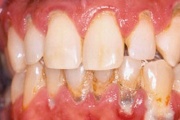

- igemed veritsevad (19)

- igemed punetavad (21)

- ige on paistes (mädapunn)

- igemed on tursunud/vohavad (17)

- puudulik suuhügieen (5)

- igemepealne hambakivi (5)

- igemealune hambakivi (4)

- halb hingeõhk / suu haiseb (12)

- halb maitse suus (12)